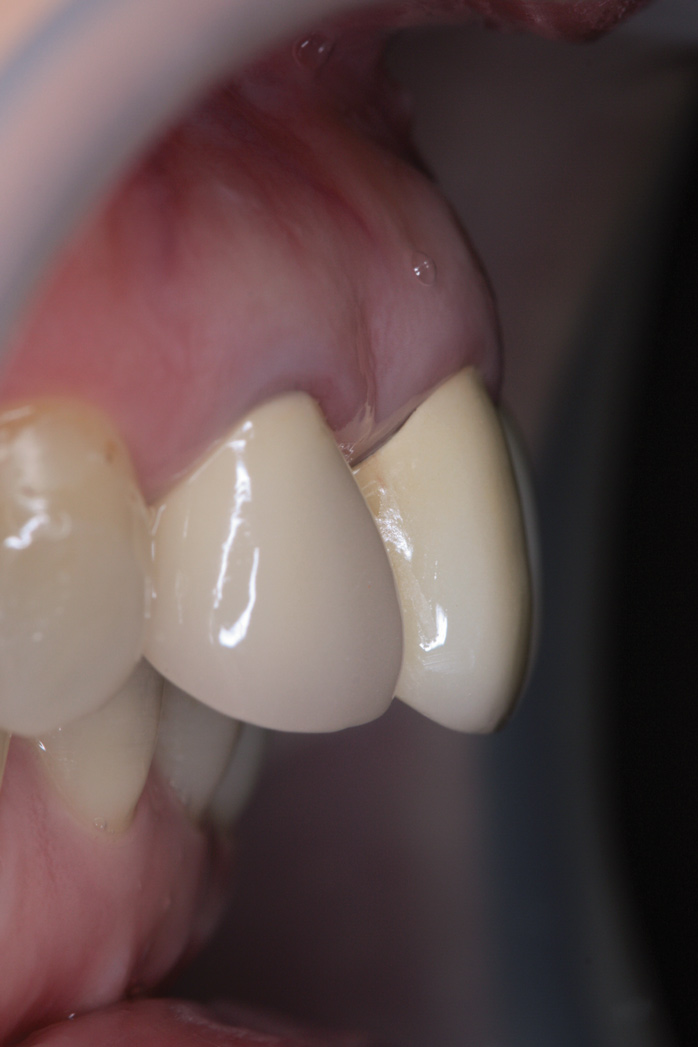

Prior to orthodontic treatment, all existing crowns were replaced by temporary crowns with proper size and shape. Disease control, including treatments for caries, periodontal disease, and pathological periapical lesions, was completed. Two months into orthodontic treatment, the No. 19 implant temporary crown was intentionally fabricated in a higher occlusal stop to increase the patient's VDO and allow orthodontic extrusion of bilateral lower posterior teeth. The No. 19 implant could serve as not only a bite opening anchor but also an excellent anchor for subsequent orthodontic intrusion-proclination of lower anterior teeth (Figure 8). Tooth No. 18 was extracted during the orthodontic treatment due to its poor prognosis.

Fig 8. Increased VDO through use of temporary crown on No. 19 implant.

Figure 8